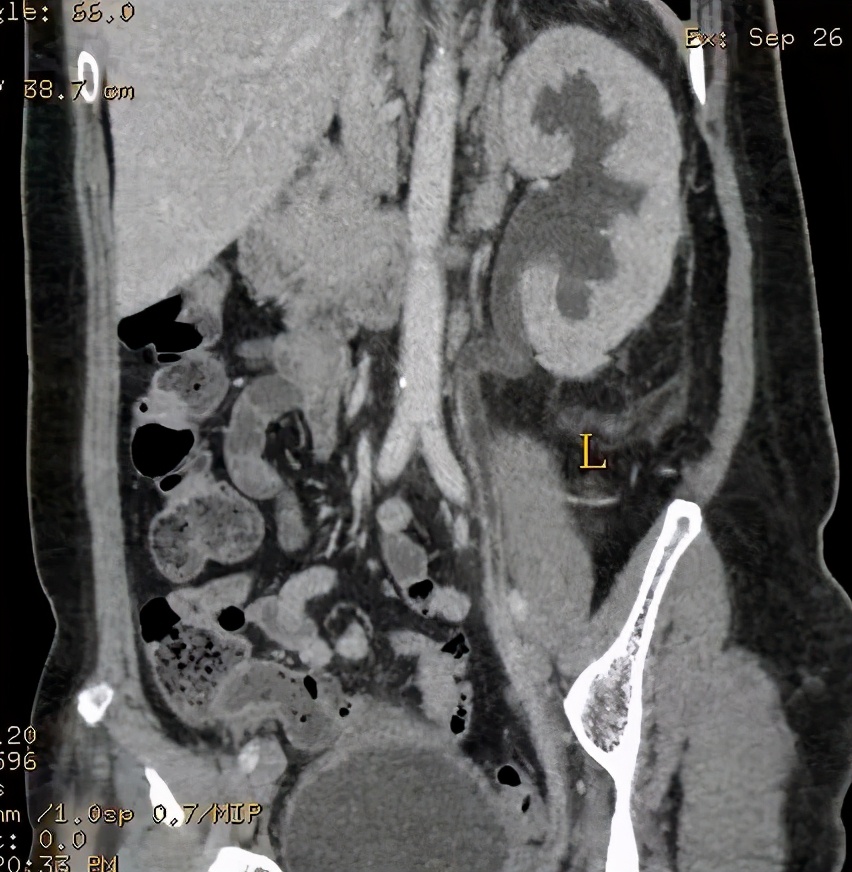

上图所示:38岁女患,有发热、脓尿等症状,临床诊断为泌尿系感染,行尿路造影检查,可见(左侧)输尿管下段管壁增粗,均匀强化,考虑输尿管炎症可能。